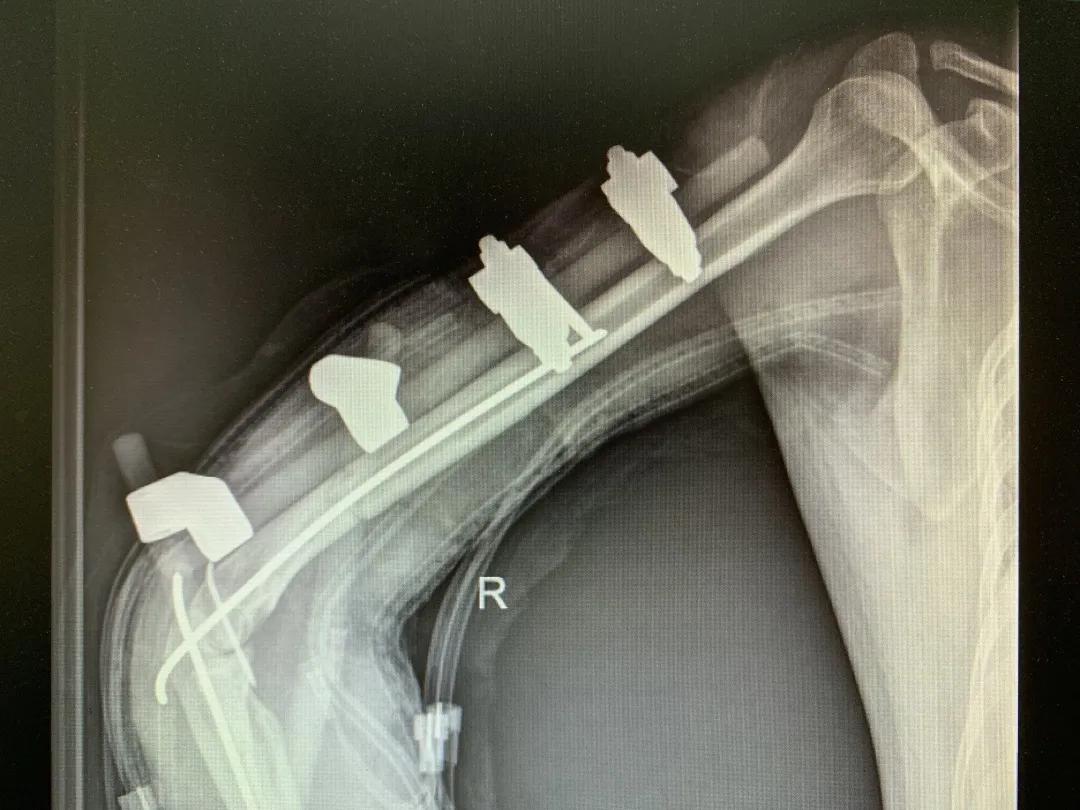

“正常的肢体都有皮肤保护着,如果没有皮肤,我们的肌肉、血管、神经、骨骼露在外面,都会发生坏死。”苑芳昌介绍,伤者的情况非常复杂,伴有多发骨折、肱骨骨折、骨关节的多发错位,还有腕部的骨折,更有血管、神经损伤。不仅如此,伤者右臂在机器里面受到绞伤,肌肉也已经大面积挫伤,各种复杂情形交织在一起甚至让手术“无从下手”。

清创、止血、接骨、将粉碎的骨块一块块拼接完整,同时给予VSD敷料负压引流。经过三次清创清除后,明确了坏死的皮肤等组织,创面好转,肉芽组织良好……